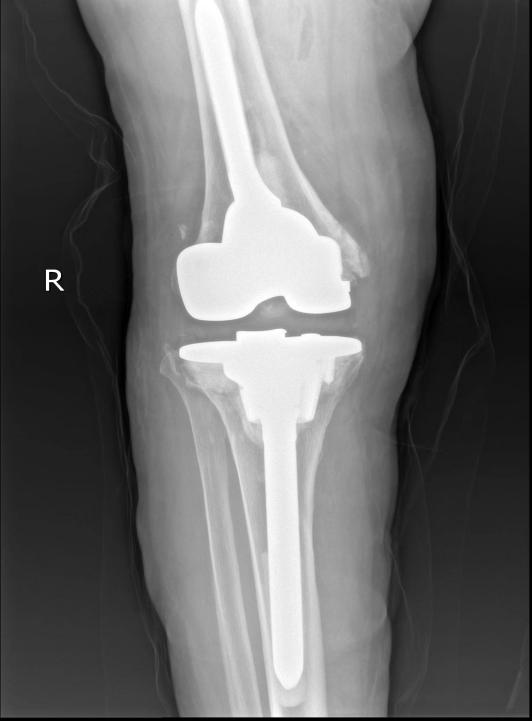

在充分做好个人防护的前提下,手术组医务人员分工协作、默契配合,整个手术过程有条不紊、十分顺利。手术完成后,李大娘被安全送返住院部单间隔离病房休养,术后X线检查发现,假体力线无偏差,髌骨轨迹良好,膝关节功能良好。李大娘和家人对治疗效果都非常满意。

12月13日,李杨教授、陈鹏副教授、彭启华医师身穿防护服、佩戴医用防护口罩、正压防护头罩、手套等防护用品,按照预定手术思路进行右侧膝关节翻修术。手术中,医务人员取出了磨损松动的胫骨、股骨侧假体和聚乙烯垫片,充分清除关节周围增生及坏死组织后,反复推敲,精心设计,将股骨和胫骨假体分别安装植入,再植入14mm聚乙烯垫片。